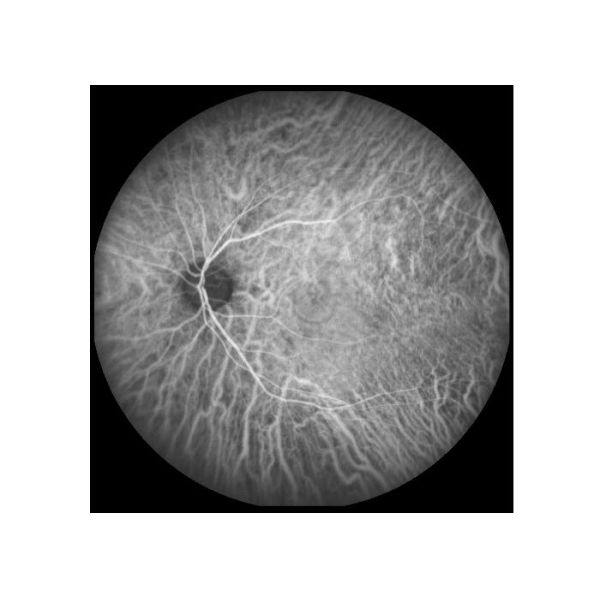

Angiografía de la fluoresceína del fondo (FFA): Cambio circulatorio retiniano |

1) “Estándar de oro” para juzgar enfermedad de la retina 2) Para reflejar la patología fisiológica de los vasos sanguíneos retinianos a los capilares 3) Para examinar completo las enfermedades desapercibidas en el examen normal del fondo |